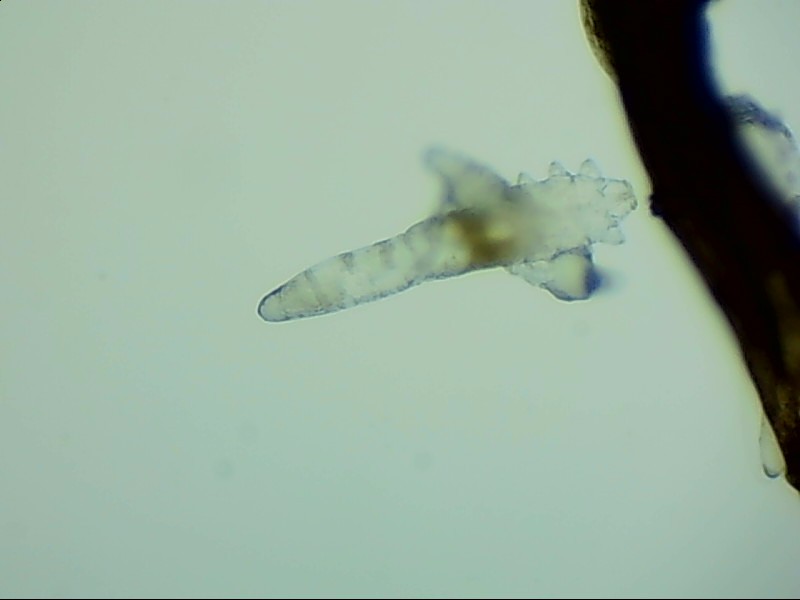

人體上寄生著兩種蠕形螨,分別是毛囊蠕形螨和皮脂蠕形螨,它們以睫毛囊上皮細(xì)胞、腺體內(nèi)脂質(zhì)為食物,因此主要寄生在面部、眼睛、頭皮等地方,其中寄生在眼睛里的蠕形螨主要活動(dòng)在睫毛毛囊、睫毛皮脂腺,以及瞼板腺里。

蠕形螨完全長(zhǎng)大也只有0.1-0.2毫米,因此肉眼難以看到它們,只有在電子顯微鏡下我們才能看到睫毛根部的一只只蠕形螨。這些螨蟲每天都很活躍,且繁殖速度極快,完成一代生活史僅需大概15天。

螨蟲無(wú)所遁形,螨蟲鏡檢:

螨蟲鏡檢主要是通過(guò)顯微鏡觀察,它能無(wú)死角放大你的睫毛,讓螨蟲無(wú)處可躲。

在檢查的時(shí)候,醫(yī)生要在每個(gè)眼瞼上拔出幾根比較典型的睫毛,然后放在光學(xué)顯微鏡下,尋找有沒(méi)有螨蟲,同時(shí)觀察螨蟲的數(shù)量多少。

如果任意一個(gè)眼瞼上螨蟲數(shù)量較多,再加上你的眼睛有局部癥狀,后續(xù)就需要進(jìn)行相應(yīng)的治療了。